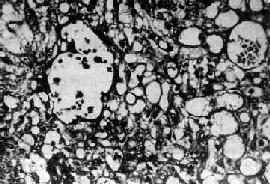

内胚窦<a href=瘤"/>

图13-23 内胚窦

呈疏松网状粘液样结构,其中有互相沟通、衬以上皮的腔隙及小囊腔,在细胞内外可见嗜酸性玻璃样小球及基底膜样物

肉眼观,肿多为单侧性,以右侧为多,一般体积较大,平均直径为15~25cm,圆或卵圆形,表面光滑。切面多为实性,质较脆,灰白或粉白色,常有出血坏死及囊性变。镜检,组织形态较复杂及特殊,主要特征有下列几点:①网状结构,是最常见的形态,由星芒状的细胞形成疏松网状结构(图13-23),其中有微型小囊或间隙,囊腔被覆扁平或立方细胞,这种结构类似胚外中胚层结构;②内胚窦样结构,立方或柱状的细胞成单层排列,包绕毛细血管,形成一血管套样结构,这种结构横切面很像肾小球,称为Schiller-Duval小体,这种小体和大鼠胎盘内的Duval内胚窦结构相似,这种结构可能是由卵黄囊衍生演变而来;③多泡性卵黄囊样结构,特征是由扁平上皮、立方或低柱状的细胞形成大小不等的囊腔,其间隔以致密的结缔组织或疏松的粘液样间质,这种结构与胚胎时期的卵黄囊(胚外内胚层)相似;④在细胞内及细胞间隙可见PAS阳性的大小不等的嗜酸性小滴,免疫组化显示这种小滴含有甲胎蛋白(AFP),正常情况下,卵黄囊可合成AFP;⑤可见腺样、乳头状及实体细胞团结构等。